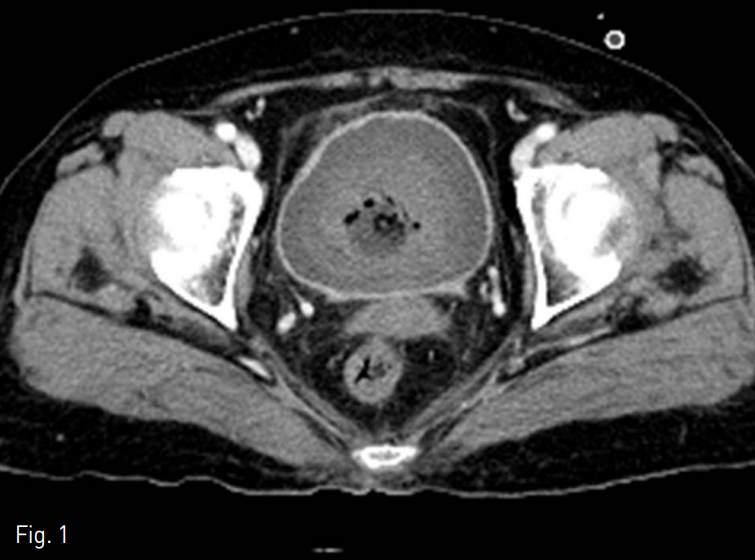

우측 총대퇴동맥을 천자하여 5 Fr sheath (Terumo, Tokyo, Japan)를 삽입한 후, pigtail catheter (Cook, Bloomington, USA)를 복부 대동맥에 위치시키고 시행한 골반동맥조영술에서 양측 총장골동맥 및 내장골동맥에 혈관 외 유출은 없었음. 5 Fr Yashiro catheter (Terumo, Tokyo, Japan)를 이용하여 좌측 내장골동맥을 선택하여 혈관조영술을 시행하였을 때, 뚜렷한 조영제의 혈관 외 유출은 보이지 않았으나 왼쪽 상방광동맥이 다소 발달되어 있어 (Fig. 2) 이를 미세도관(Progreat, Terumo, Tokyo, Japan)과 미세유도철사(GT wire, Terumo, Tokyo, Japan)로 초선택한 다음 gelfoam으로 색전하였음. 이후 오른쪽 내장골동맥을 선택하려 하였으나 severe atherosclerosis로 실패함.

Fig. 2

The left internal iliac angiogram shows no evidence of extravasation of contrast media in the superior vesical artery (arrow).